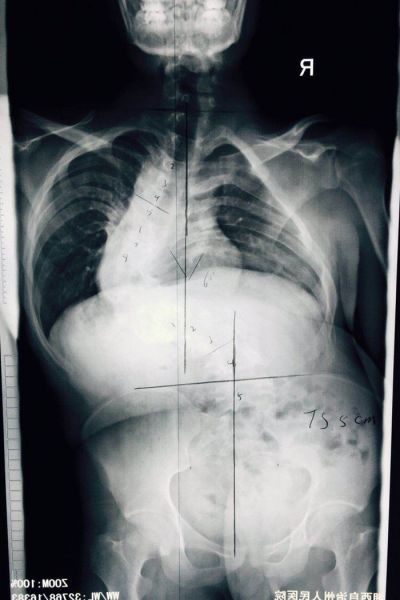

患者龙某,男,22岁,苗族,凤凰腊尔山人,未婚,精准扶贫户。自幼双肩不平,躯干倾斜20余年。入院就诊后检查发现:龙某身高146cm,双肩不等高,躯干左偏,后背剃刀背高度约12cm,胸廓畸形并与骨盆贴合,腹腔挤压明显。完善全脊柱正侧位X片、Beding相、顶点支撑相提示脊柱胸、腰段侧、后凸各约90°,椎体旋转扭成麻花型,椎体结构完全改变,相邻血管、神经也随之成角畸形。患者本人说,因为脊柱严重弯曲,除了基本生活很难自理外,疾病导致的身体畸形,走在路上所受到异样的眼光,比疾病本身更令人难过。因此他强烈要求手术,因为这是他唯一改变命运的机会……

患者于4月21日在全麻下行脊柱后路固定、截骨、矫形、植骨融合术,手术历时12个小时,过程基本顺利,完整达到手术目的。后经过一个多月的积极神经康复锻炼,患者目前基本恢复。患者妈妈激动的说:“孩子长高了,现在和我一样高了,背也直了!”。而且经过术后评估检测,患者伤口一级愈合,身高增长7cm,剃刀背高度下降8cm,双肩等高,躯干已基本平衡,脊柱畸形得到满意矫正,目前患者及家属已经满意出院。